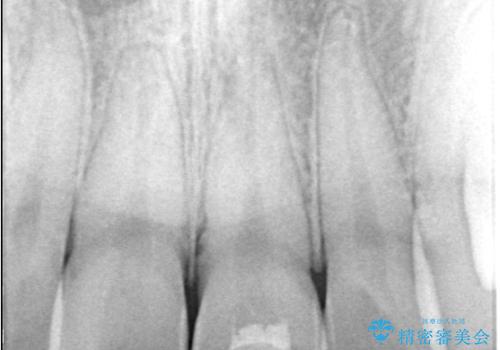

- 歯冠破折により点状露髄を認めました。破折から1週間以内であったこと、また歯髄診断により生活反応が良好で保存可能と判断したため、VPT(生活歯髄療法)を行い神経の保存を試みました。

神経の状態が良好に保たれていることを確認した後、オールセラミッククラウンによる審美修復を行いました。